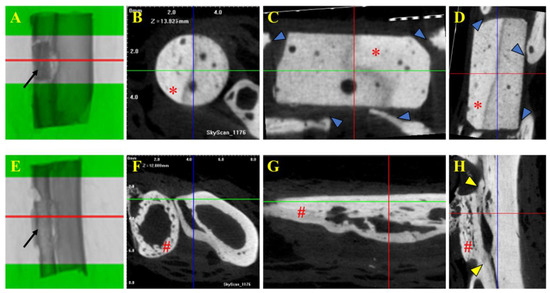

3.4. Micro-Computed Tomography and Histological Evaluations

In the μCT images, no osseointegration was observed between the β-TCP implant and the bone in the animals from Group A. In contrast, visible osseointegration between the allogeneic cortical bone graft and the bone was evident in the animals from Group B. In Group A, the implants were well positioned with no signs of mobility at their initial insertion sites. Although the edges of the recipient bone grew towards the implant, they did not integrate with the ceramic to form a single, continuous structure, as seen in the images. The cylindrical blocks of the implants retained their original size, and no clear signs of resorption were observed. However, some small radiolucent circular dots were noted inside the implant, contrasting with the rest of the structure. These could potentially represent the early stages of implant resorption or areas of greater porosity within the material (Figure 4).

In Group B, the bone grafts exhibited evidence of osseointegration, as well as the early stages of bone remodeling. The edges of the recipient bone grew towards the graft, eventually connecting and forming a single, continuous structure, visible in the images. The grafts were well positioned and showed no signs of mobility. There also appeared to be integration with the adjacent bone, the ulna, where the two structures could be observed in direct contact (Figure 4).

Figure 4. Tomographic images of selected fragments of animals from Group A (β-TCP; (AD)) and Group B (cortical allogeneic bone graft; (EH)). Tomographic images of 2 cm bone with β-TCP implant (Group A) and bone graft (Group B). (A,E) Middle part of the implant and graft as region of interest (ROI) for μCT analysis and acquisition of cross-sectional images. Note the implant and bone graft inserted in the receptor bones (black arrows in (A) and (E), respectively). (B,F) Trans-axial cut. (C,G) Coronal cut. (D,H) Sagital cut. * β-TCP implant. # Allogenous cortical bone graft. Note that there is no implant–bone osteointegration seen in μCT images of Group A (blue arrows in (C,D)), but on the contrary, there is positive osteointegration between the bone graft and bone, as shown in (H) (yellow arrows).